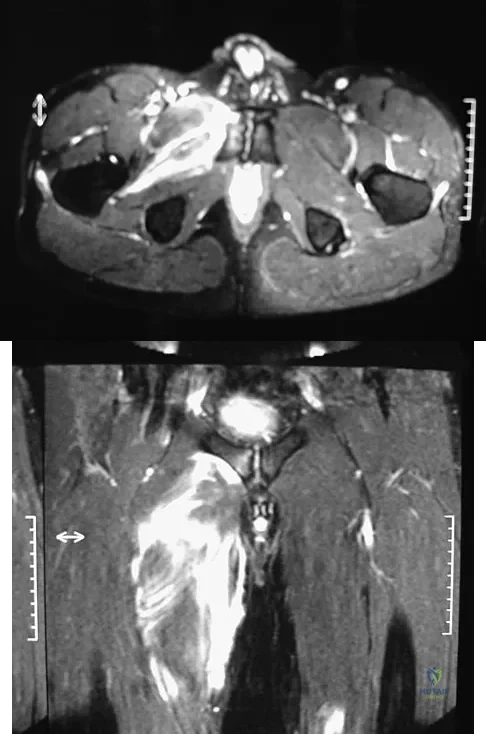

A 36-year-old professional baseball player reports the acute onset of severe right groin pain while attempting to avoid being hit by a baseball while at bat. Examination reveals tenderness, soft-tissue swelling, and ecchymosis in the right groin extending over the medial thigh. MRI scans are shown in Figures 8a and 8b. Management should consist of

Explanation